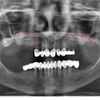

Implant tedavisi